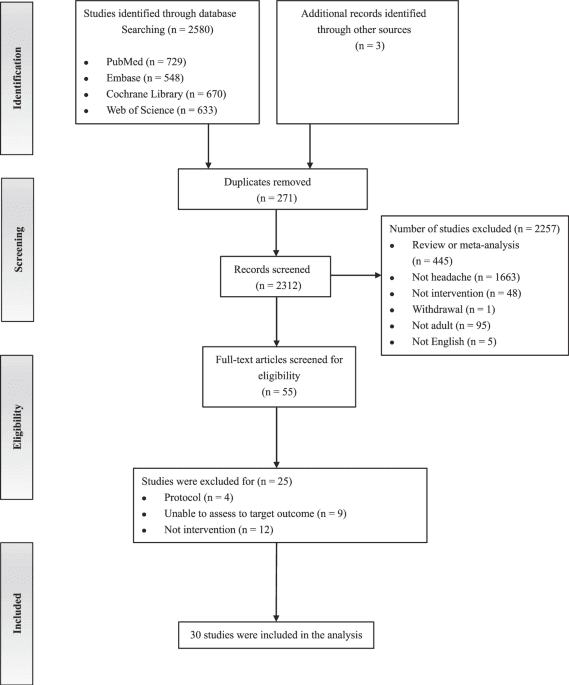

PursueCare, a company that provides personalized virtual addiction treatment, announced the re-release of FDA-cleared RESET and RESET-O, prescription digital therapeutics for substance use disorder and opioid use disorder.RESET and RESET-O were initially developed and…